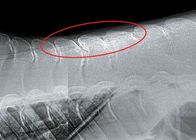

●X線撮影